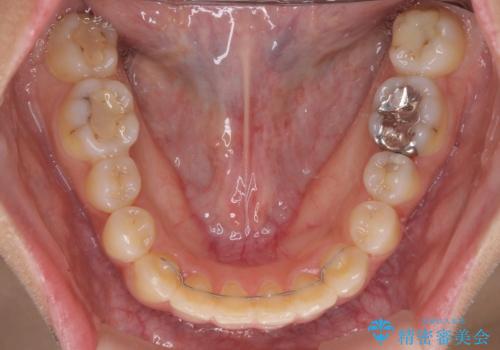

前歯の突出感とデコボコ インビザラインで改善

- 上下前歯のデコボコを気にして来院された患者様です。

インビザラインによる上下歯列の側方拡大と後方移動、IPR(歯と歯の間を削る)にるスペースの獲得により歯列を整えることとしました。

右上の小臼歯は歯根癒着をしており、様々な方法を試みるも動かすことができませんでした。

それでも奥歯のかみ合わせに不自由はなく、歯列をきれいに整えることができました。